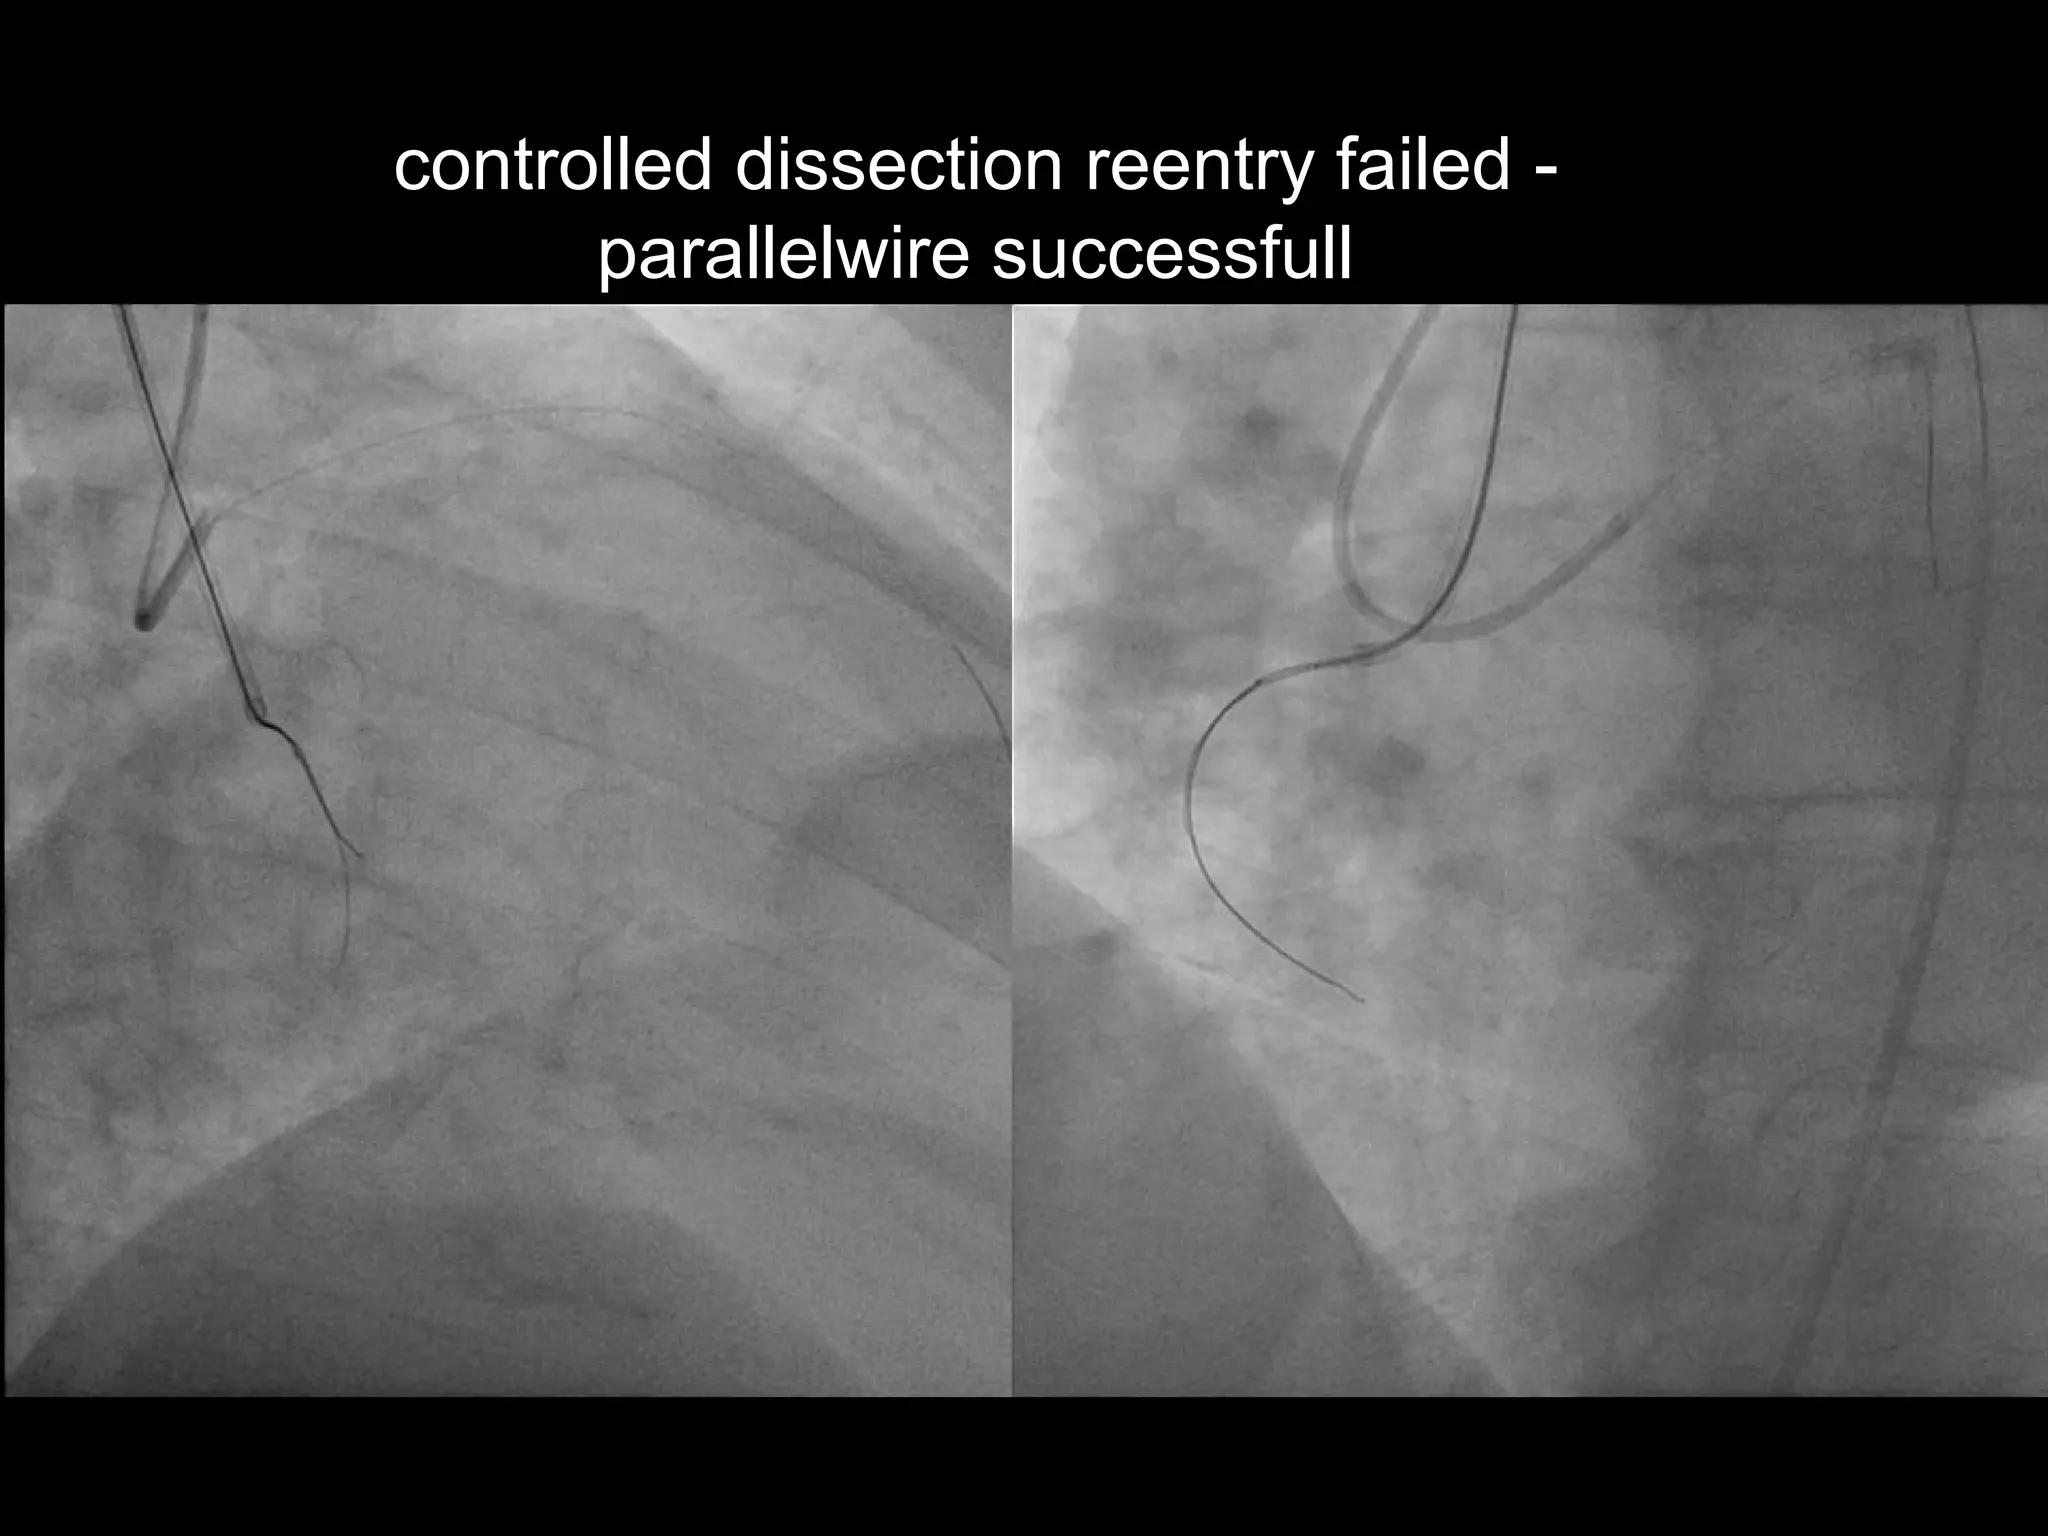

controlled dissection reentry failed -

parallelwire successfull